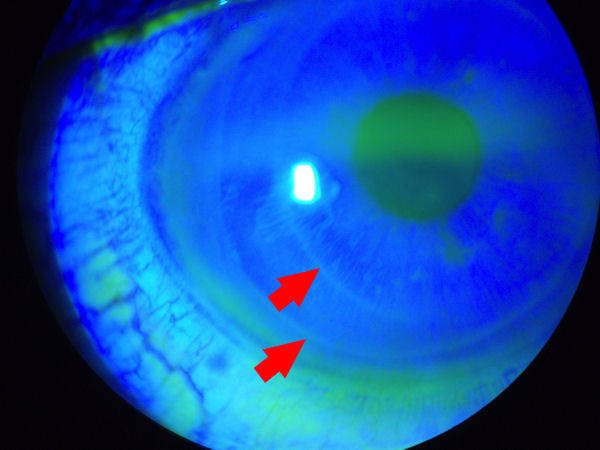

Ниже представлены две фотографии глаза с отслоившимся лоскутом LASIK. Лоскут отслоился во время установки контактных линз - еще один пример того, насколько хрупкой становится роговица после операции LASIK. На первом снимке вы можете отчетливо видеть краситель, который проник в пространство между лоскутом и нижележащей роговицей. Пациенты, перенесшие операцию LASIK, подвергаются пожизненному риску смещения лоскута, инфицирования, врастания эпителия, ДЛК и других осложнений. (Нажмите на фото, чтобы увеличить изображение). На втором изображении красная стрелка указывает на темную область, где лоскут не прикреплен к роговице. Это пространство проходит по краю лоскута.